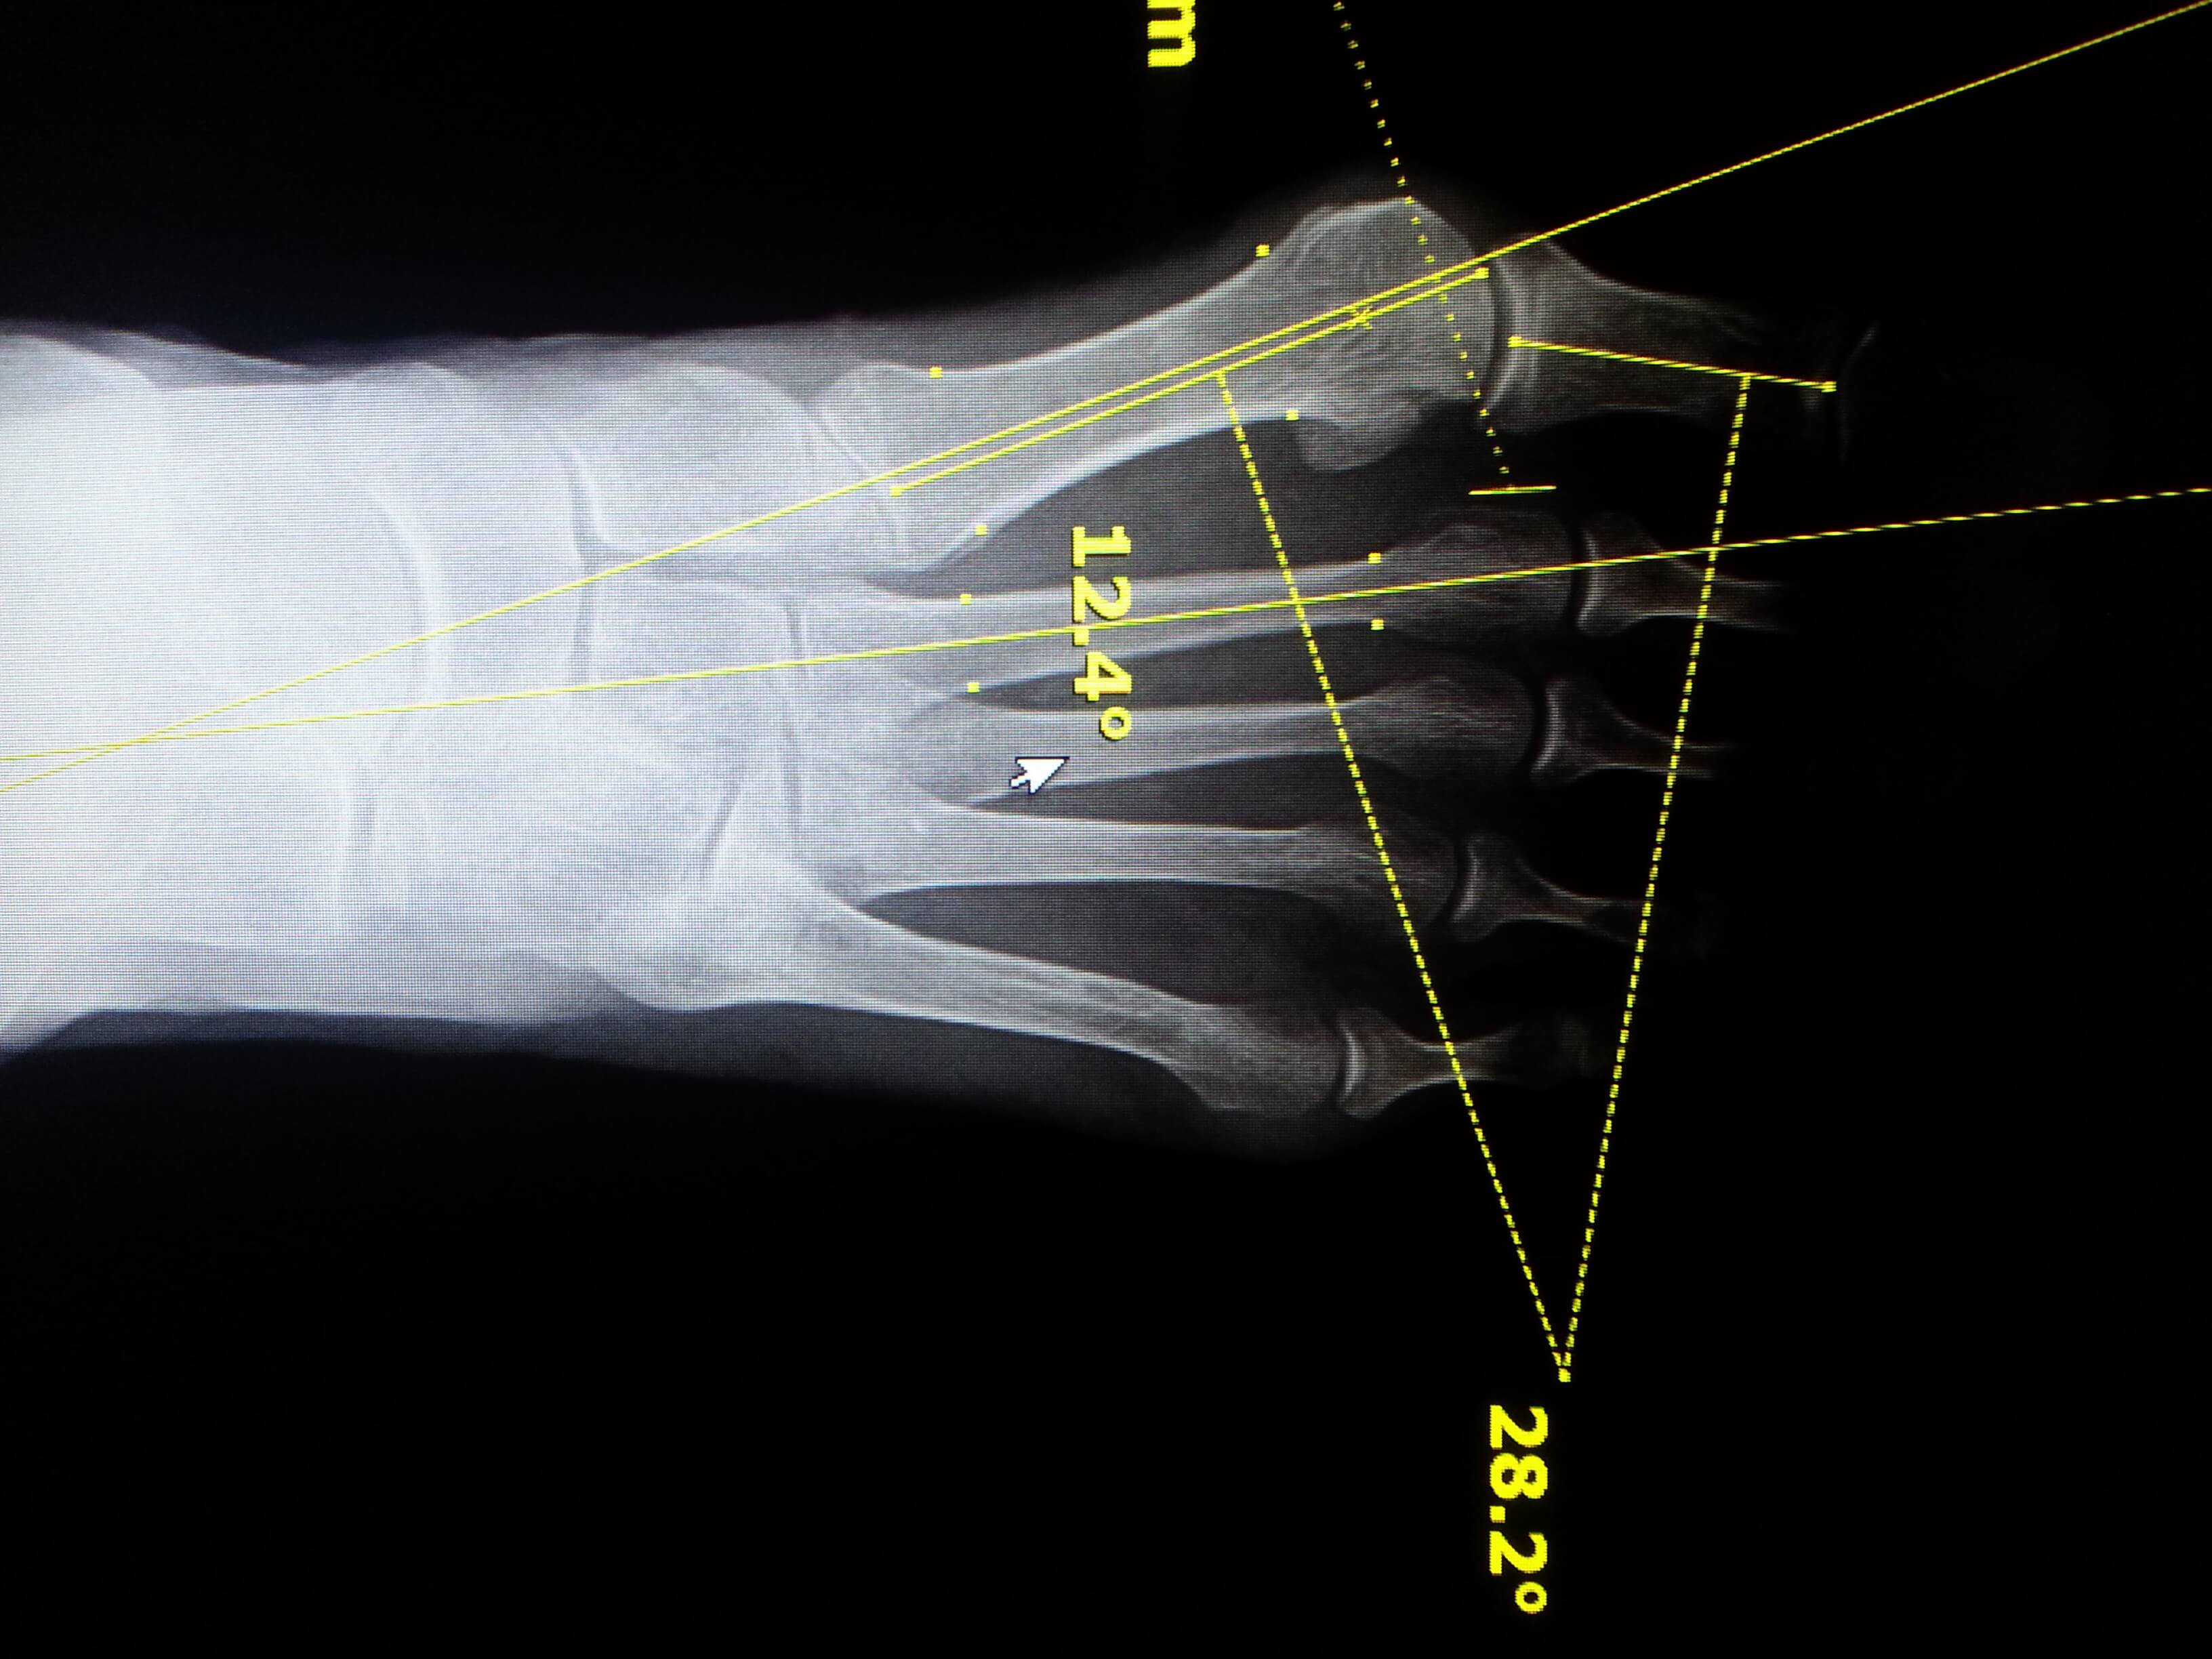

From www.sciencephoto.com

Bunion surgery assessment, Xrays Stock Image C033/7259 Science What Does A Bunion Look Like On X Ray Bunionettes are visible on clinical examination as an erythematous swelling overlying the 5 th metatarsal head. Ultrasound is sensitive enough to detect urate crystals in an affected joint. They may be tender on palpation. What Does A Bunion Look Like On X Ray.